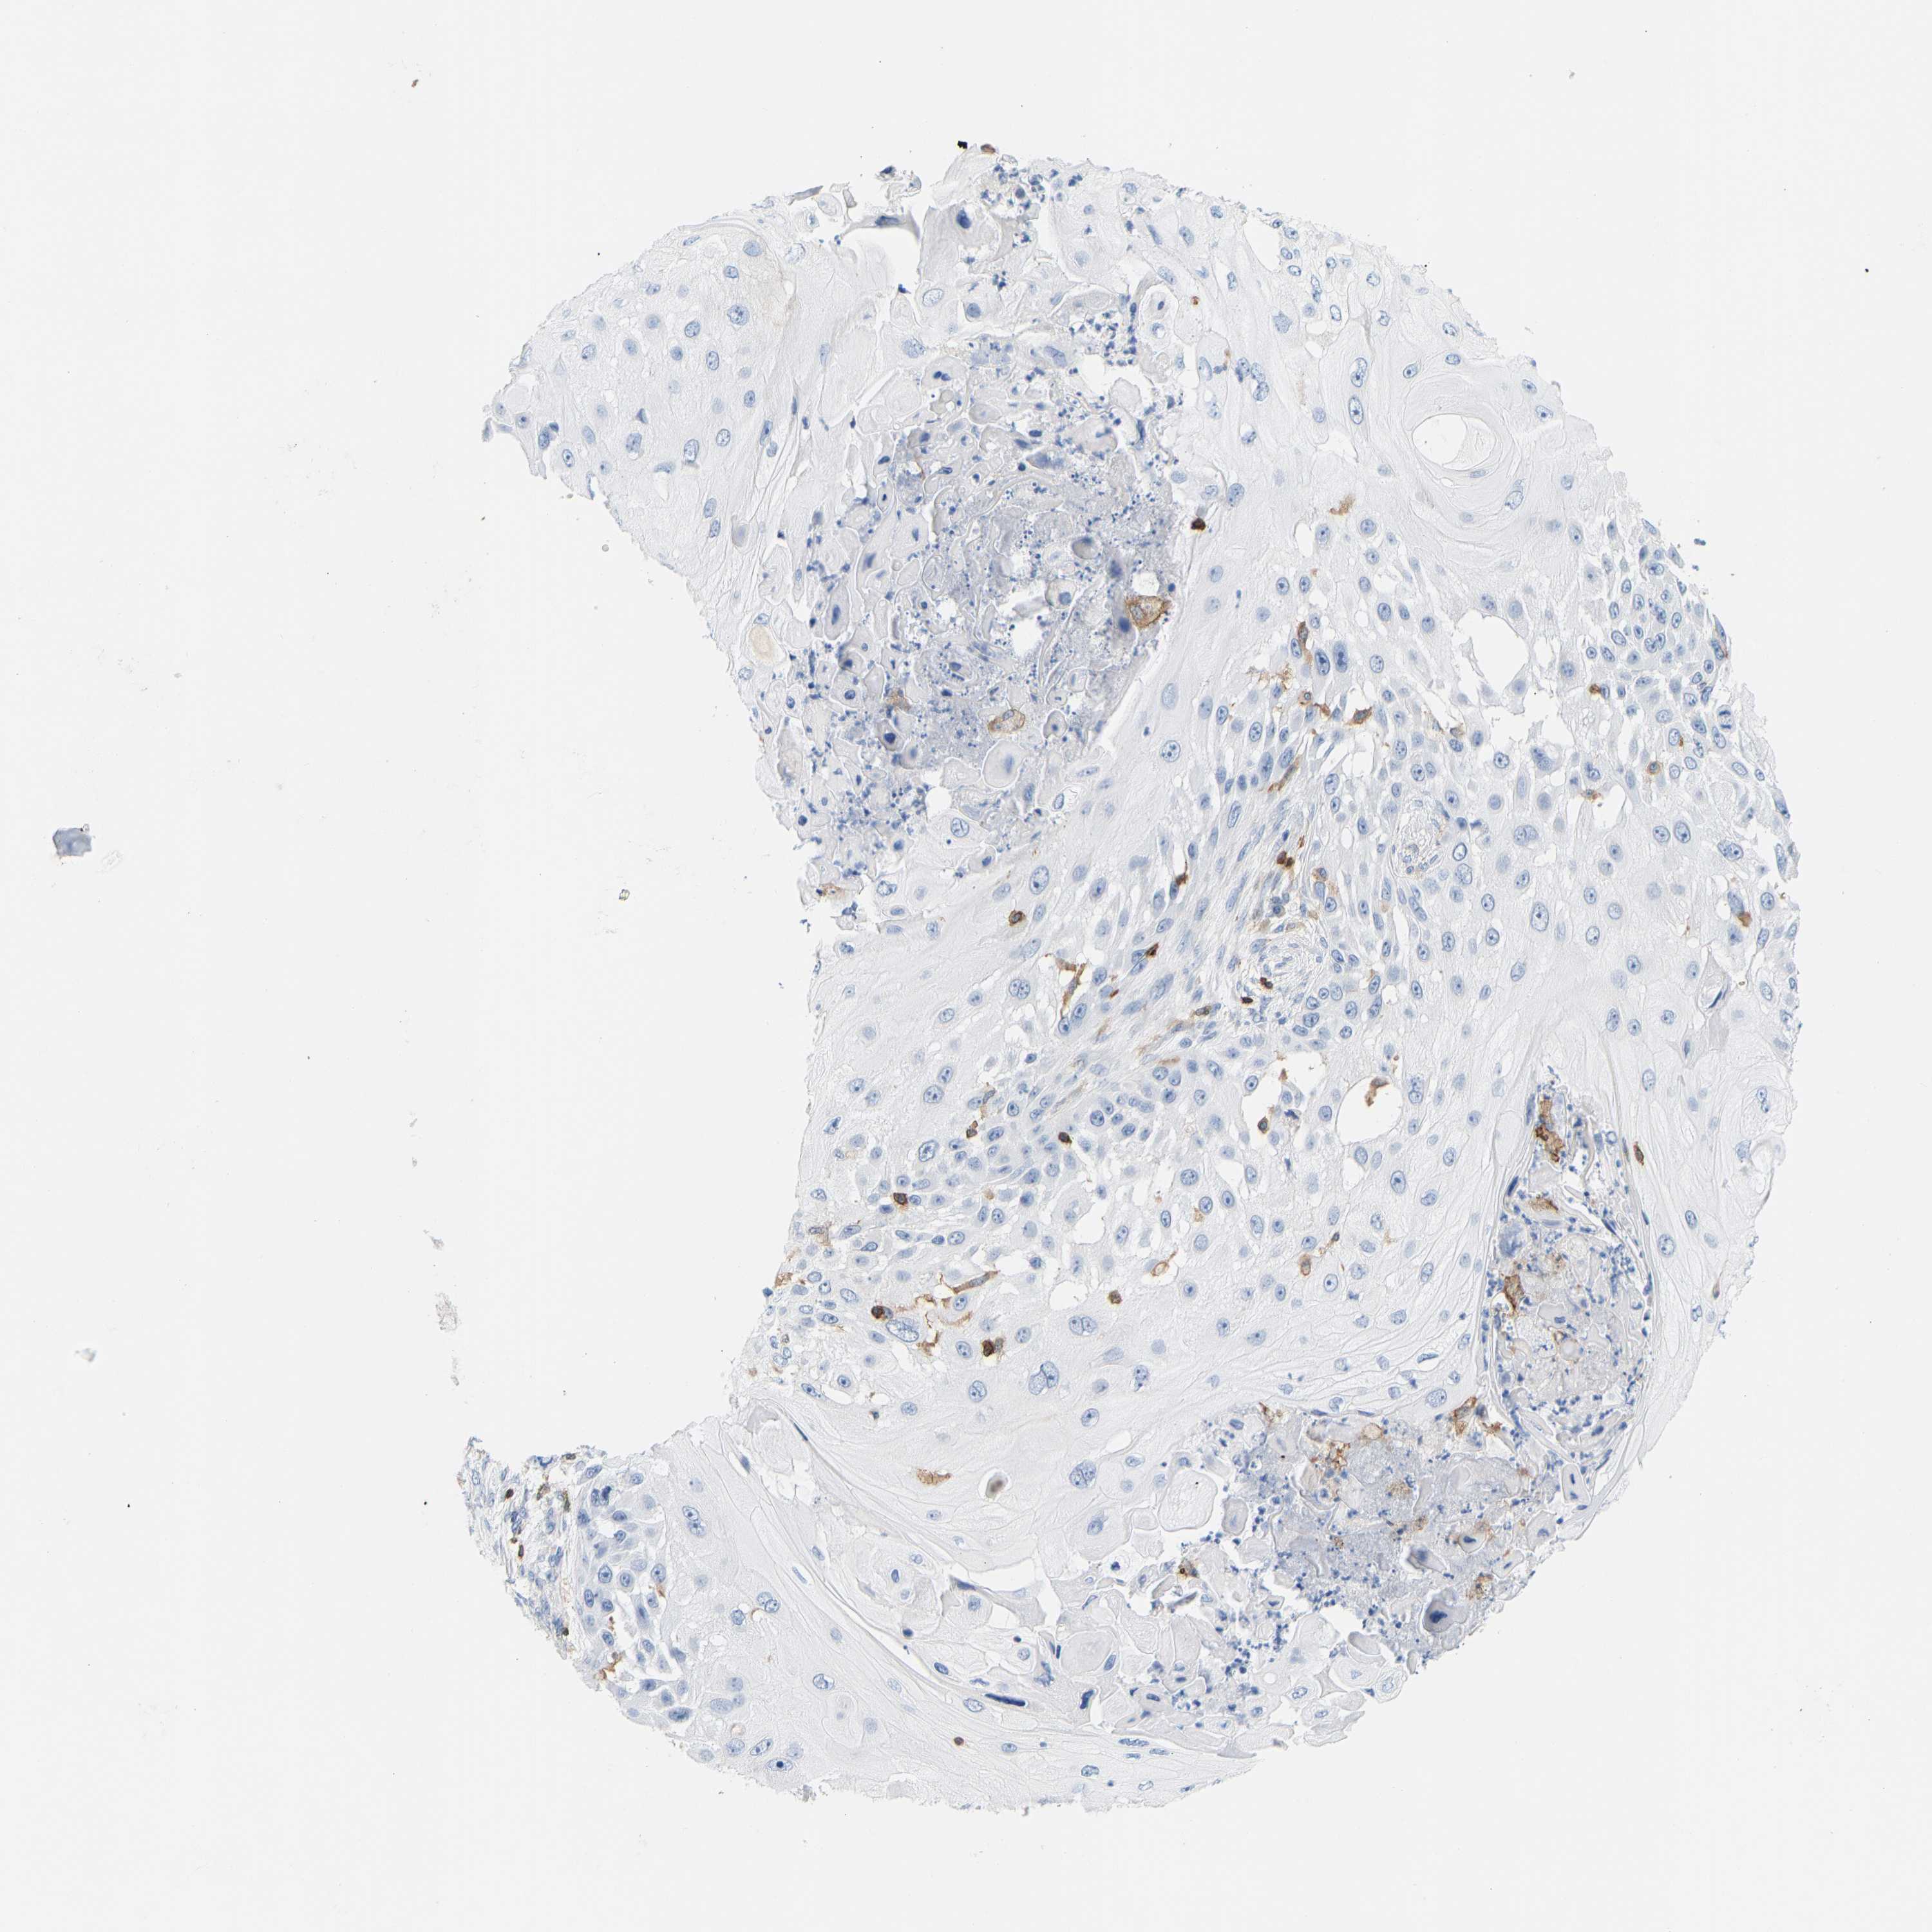

SKIN CANCER - Protein expressioni

A mouse-over function shows sample information and annotation data. Click on an image to view it in a full screen mode. Samples can be filtered based on level of antibody staining by selecting one or several of the following categories: high, medium, low and not detected. The assay and annotation is described here.

Each image is clickable and will lead to virtual microscopy that enables deeper exploration of all samples and also displays staining intensity scores, fraction scores and subcellular localization as well as patient and tissue information for each sample.

Squamous cell carcinoma, NOS